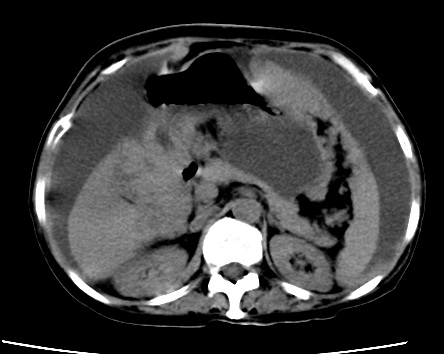

标题: CT23975:女61岁,腹部不适,明显消瘦 [打印本页]

标题: CT23975:女61岁,腹部不适,明显消瘦

既往5年前卵巢癌行子宫及附件切除,右乳癌术后一年,考虑腹膜转移?

大量腹水,考虑腹膜转移。肝脏低密度灶。1囊肿,2转移。

1)结合病史,考虑腹膜及网膜转移瘤。2)肝脏多发性低密度灶,不排除转移瘤。3)大量腹水。

考虑卵巢癌行子宫术后复发,并肝、腹腔 、大网膜转移可能性大。

大量腹水。